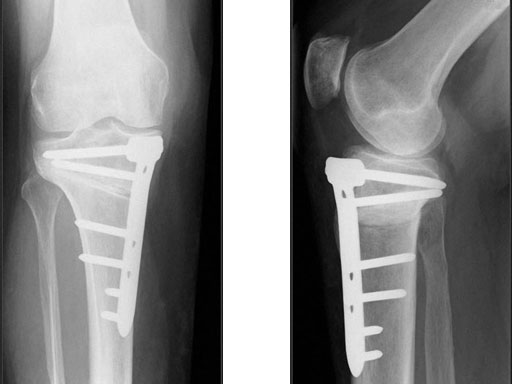

A 68-year-old female.

Case provided by Alex Staubli, Luzern, CH

The correction is planned on a long-leg standing x-ray. After surgery, the mechanical axis should pass through a point 63% on the lateral side of the total width of the tibial plateau in the frontal plane. A transverse or slightly oblique incision is used to avoid damage to the saphenous nerve. The distal fibers of the medial collateral ligament are detached from the tibia. Under fluoroscopic control, two wires are placed in the proximal tibia marking the transverse osteotomy plane. The cut usually starts at the upper margin of the pes anserinus and ends at the tip of the fibula on the lateral side. The wires are placed exactly parallel to the tibial plateau thus taking into consideration the individual tibial slope of the patient. An incomplete cut of the posterior two-thirds of the proximal tibia is performed with an oscillating saw guided by the wires. Continuous irrigation avoids burn injury to the bone. A second osteotomy is now performed in the anterior third of the tibia in an angle of 100 ending above the patellar tendon insertion. A smaller saw blade is used and the complete anterior cortex is cut exactly in the frontal plane. The osteotomy is now gradually opened by inserting flat chisels or a spreader-chisel into the posterior osteotomy cleft. This process may take some minutes and can usually be completed without fracture of the lateral cortex. A bone spreader is now placed in the posteromedial edge of the tibia and the chisels are removed. The leg is extended and the correction is checked with the fluoroscope. A long metal rod is placed between center of the hip joint and center of the ankle joint. The projection of this rod should be at the planned point of correction on the tibial plateau lateral of the midline. Eccentric collapse of the medial joint space may cause accidental overcorrection. In this case pressure on the foot may simulate loading and body weight. The correction can be fine-tuned by opening or closing the spreader. The TomoFix Medial Tibia Plate is now placed in a subcutaneous pocket. The implant is precontoured and usually fits well to the bone surface. The distance holders avoid compression of the medial collateral ligament and the pes anserinus. Three proximal bolts are placed near the subchondral sclerosis zone. The position of the bolts is adapted to the anatomy of the proximal tibia giving optimum purchase for the bolts. An oblique lag screw is inserted distal to the osteotomy. This screw in the first combination hole allows careful compression of the lateral osteotomy hinge and pretensioning of the implant. A stab incision is created on the shaft and the implant is fixed monocortically with bolts. The lag screw and the distance holders are replaced by bolts. The medial collateral ligament is released longitudinally to reduce medial compartment pressure and the wound is closed in layers. An overflow drain may be used. Clinical and experimental work has proven that when this technique is closely followed, corrections up to and over 15 mm can be performed without bone grafting or use of bone substitutes.